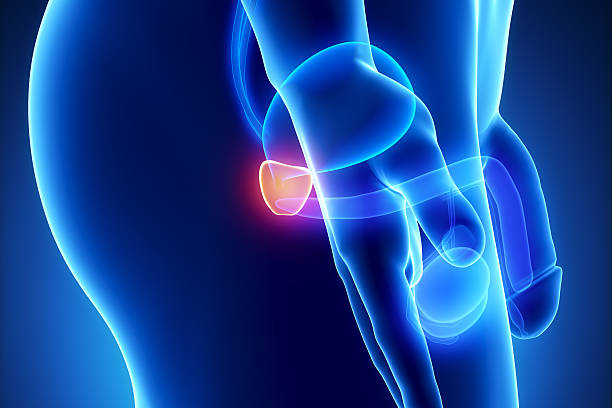

남성 생식기의 요로계와 직접적 연관이 있는 전립선은 사과 모양으로 배꼽 아래쪽에 위치해 있으며 상당히 중요한 역할을 하고 있습니다. 전립선은 사정을 조절하고, 정자의 움직임을 돕는 전립선 분비액을 만들어냅니다. 이 분비액은 정자의 영양 공급과 이동에 필수적인 성분을 포함하고 있습니다. 또한, 전립선은 방광을 둘러싸고 있는 방광 경화근과 골반 바닥 근육에 대한 지지 구조 역할을 할 수 있어 상당히 중요하나 전립선에도 암이 발병될 수 있어 초기에 원활한 대응을 해야만 합니다. 그럼 이번 시간에는 전립선암 초기증상에 대해 자세히 정리해보겠습니다.